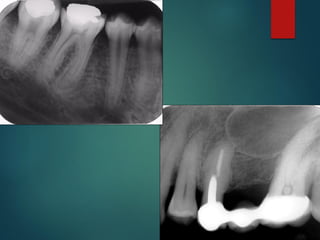

Clasificación

Radiográfica De las

Caries

 Incipiente de esmalte

 De esmalte

 Dentinaria superficial

 Dentinaria profunda

 Sobreproyectada en cámara pulpar

 Penetrante

Clasificación Radiográfica

De Las Caries

Diagnostico Radiografico de Caries